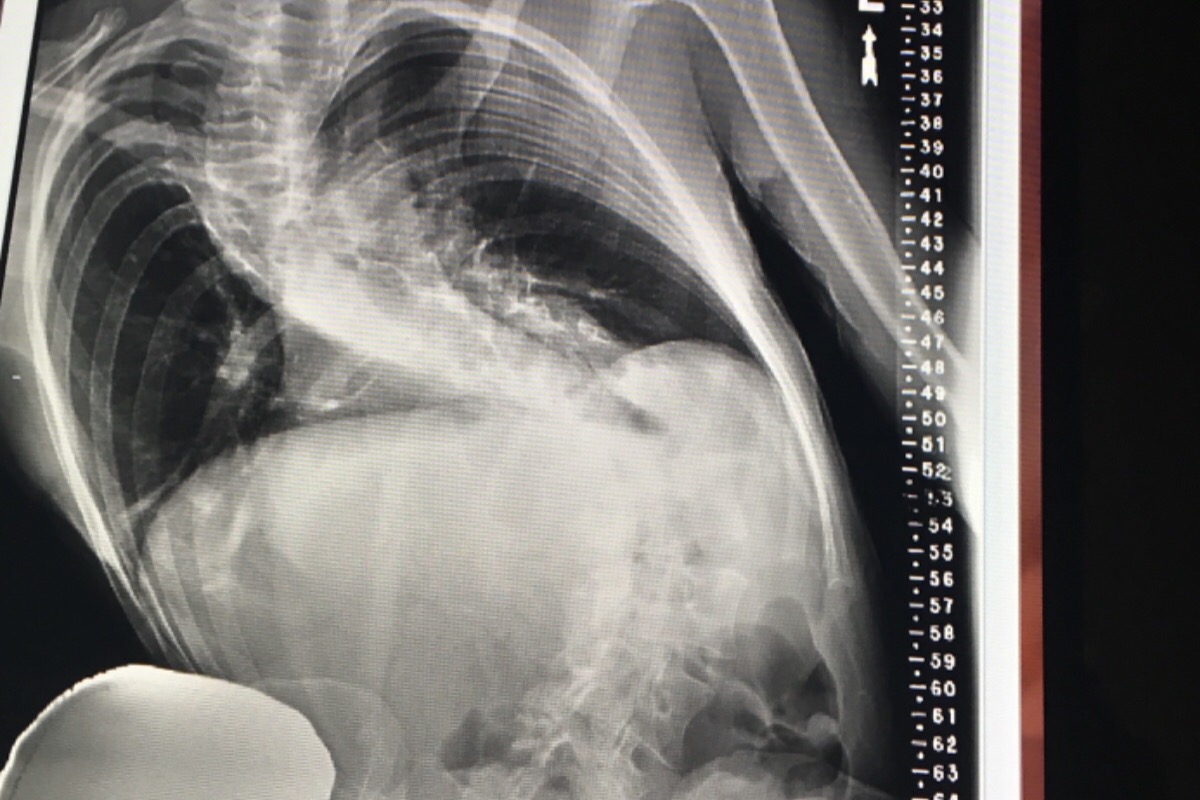

She has only until the end of the year to get limber enough for the one truly beneficial (not all death& paralyzation risksx3!!)treatment program to fit her with a high maintenance bracing system. This goes hand in hand with the Schroth physical Therapy regimen, which is arduous and rigorous to say the least. She is eligible right now, but with multiple areas of spinal fusion, the only means of gaining any ground in this regard, would be to comply with her chiropractors recommendation and go in for subluxation and orthogonal atlas adjustments(as well as ARP wave treatment{electric impulse treatment}) at $75/visit, 3x week.

There’s NO WAY she can afford even 1xweek as it stands, and she is very quickly running out of time. She has always amazed her specialists with her ability to conform to whatever stimuli she is exposed to, “elastica” is what 4 doctors called her over time& in fact, being stuck in a wheelchair for 3 months and being forbidden to engage in stretching/yoga- is what initiated this severe nose dive.

At the end of the year, due to the damage the efforts to get limber will inevitably subject her spine to, if She’s unable to get in to see the therapist frequently enough, the progress will not be substantial enough for Spine-Cor, and neither the terrifying surgical option NOR spine Cor will accept her with more damage to undo. She is already the most challenging case either practice (UCSF/Spine-Cor) has ever been faced with to date.